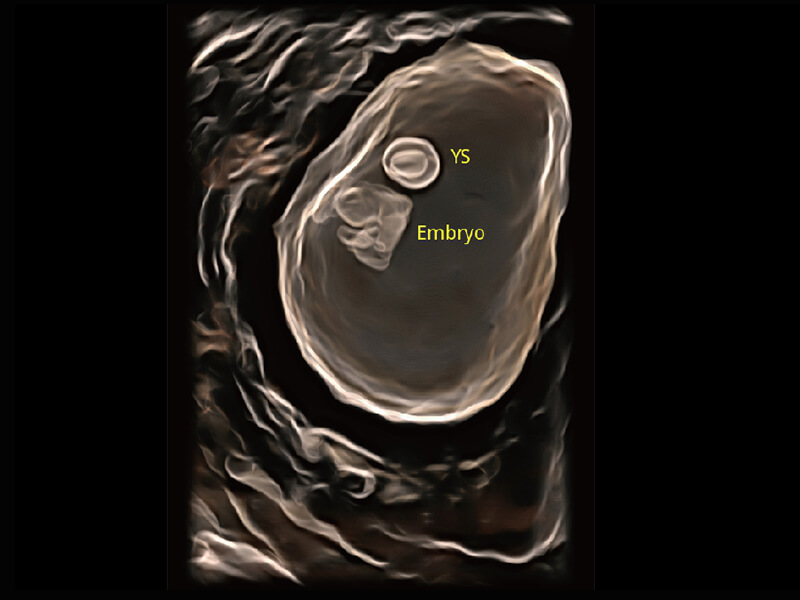

创新的超宽频带技术,为容积成像带来优质的二维图像基础,为您呈现更丰富的结构细节,栩栩如生地展示宝宝的宫内形态以及各种组织的立体结构。